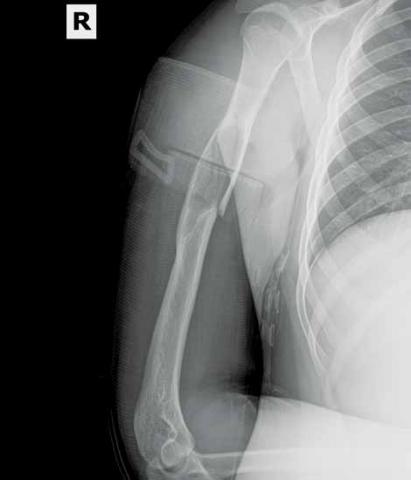

The radiograph (Figure 2) revealed a minimally displaced pathologic fracture (red arrow) through the midshaft of the humerus, which resulted from a space-occupying lesion (green arrow) in the humeral diaphysis. Since the radial nerve is commonly affected in this type of injury due to its close proximity to the humeral midshaft, careful neurologic assessment at the wrist and hand is essential. Injury to the nerve can occur during the fracture or reduction of the fracture, causing weakness in the extensors of the hand and numbness in the first dorsal web space. The incidence of radial nerve palsy in midshaft fractures of the humerus is 16%.1

In nondisplaced or minimally displaced fractures of the humeral midshaft, conservative management with a U-shaped (sugar-tong) splint from axilla to shoulder with elasticized wrap and sling is recommended. Surgical management is indicated in comminuted, significantly displaced, nonreducible, pathologic cases or in fractures resulting in neurovascular compromise. The patient in this case was referred to an orthopedic surgeon for open treatment.